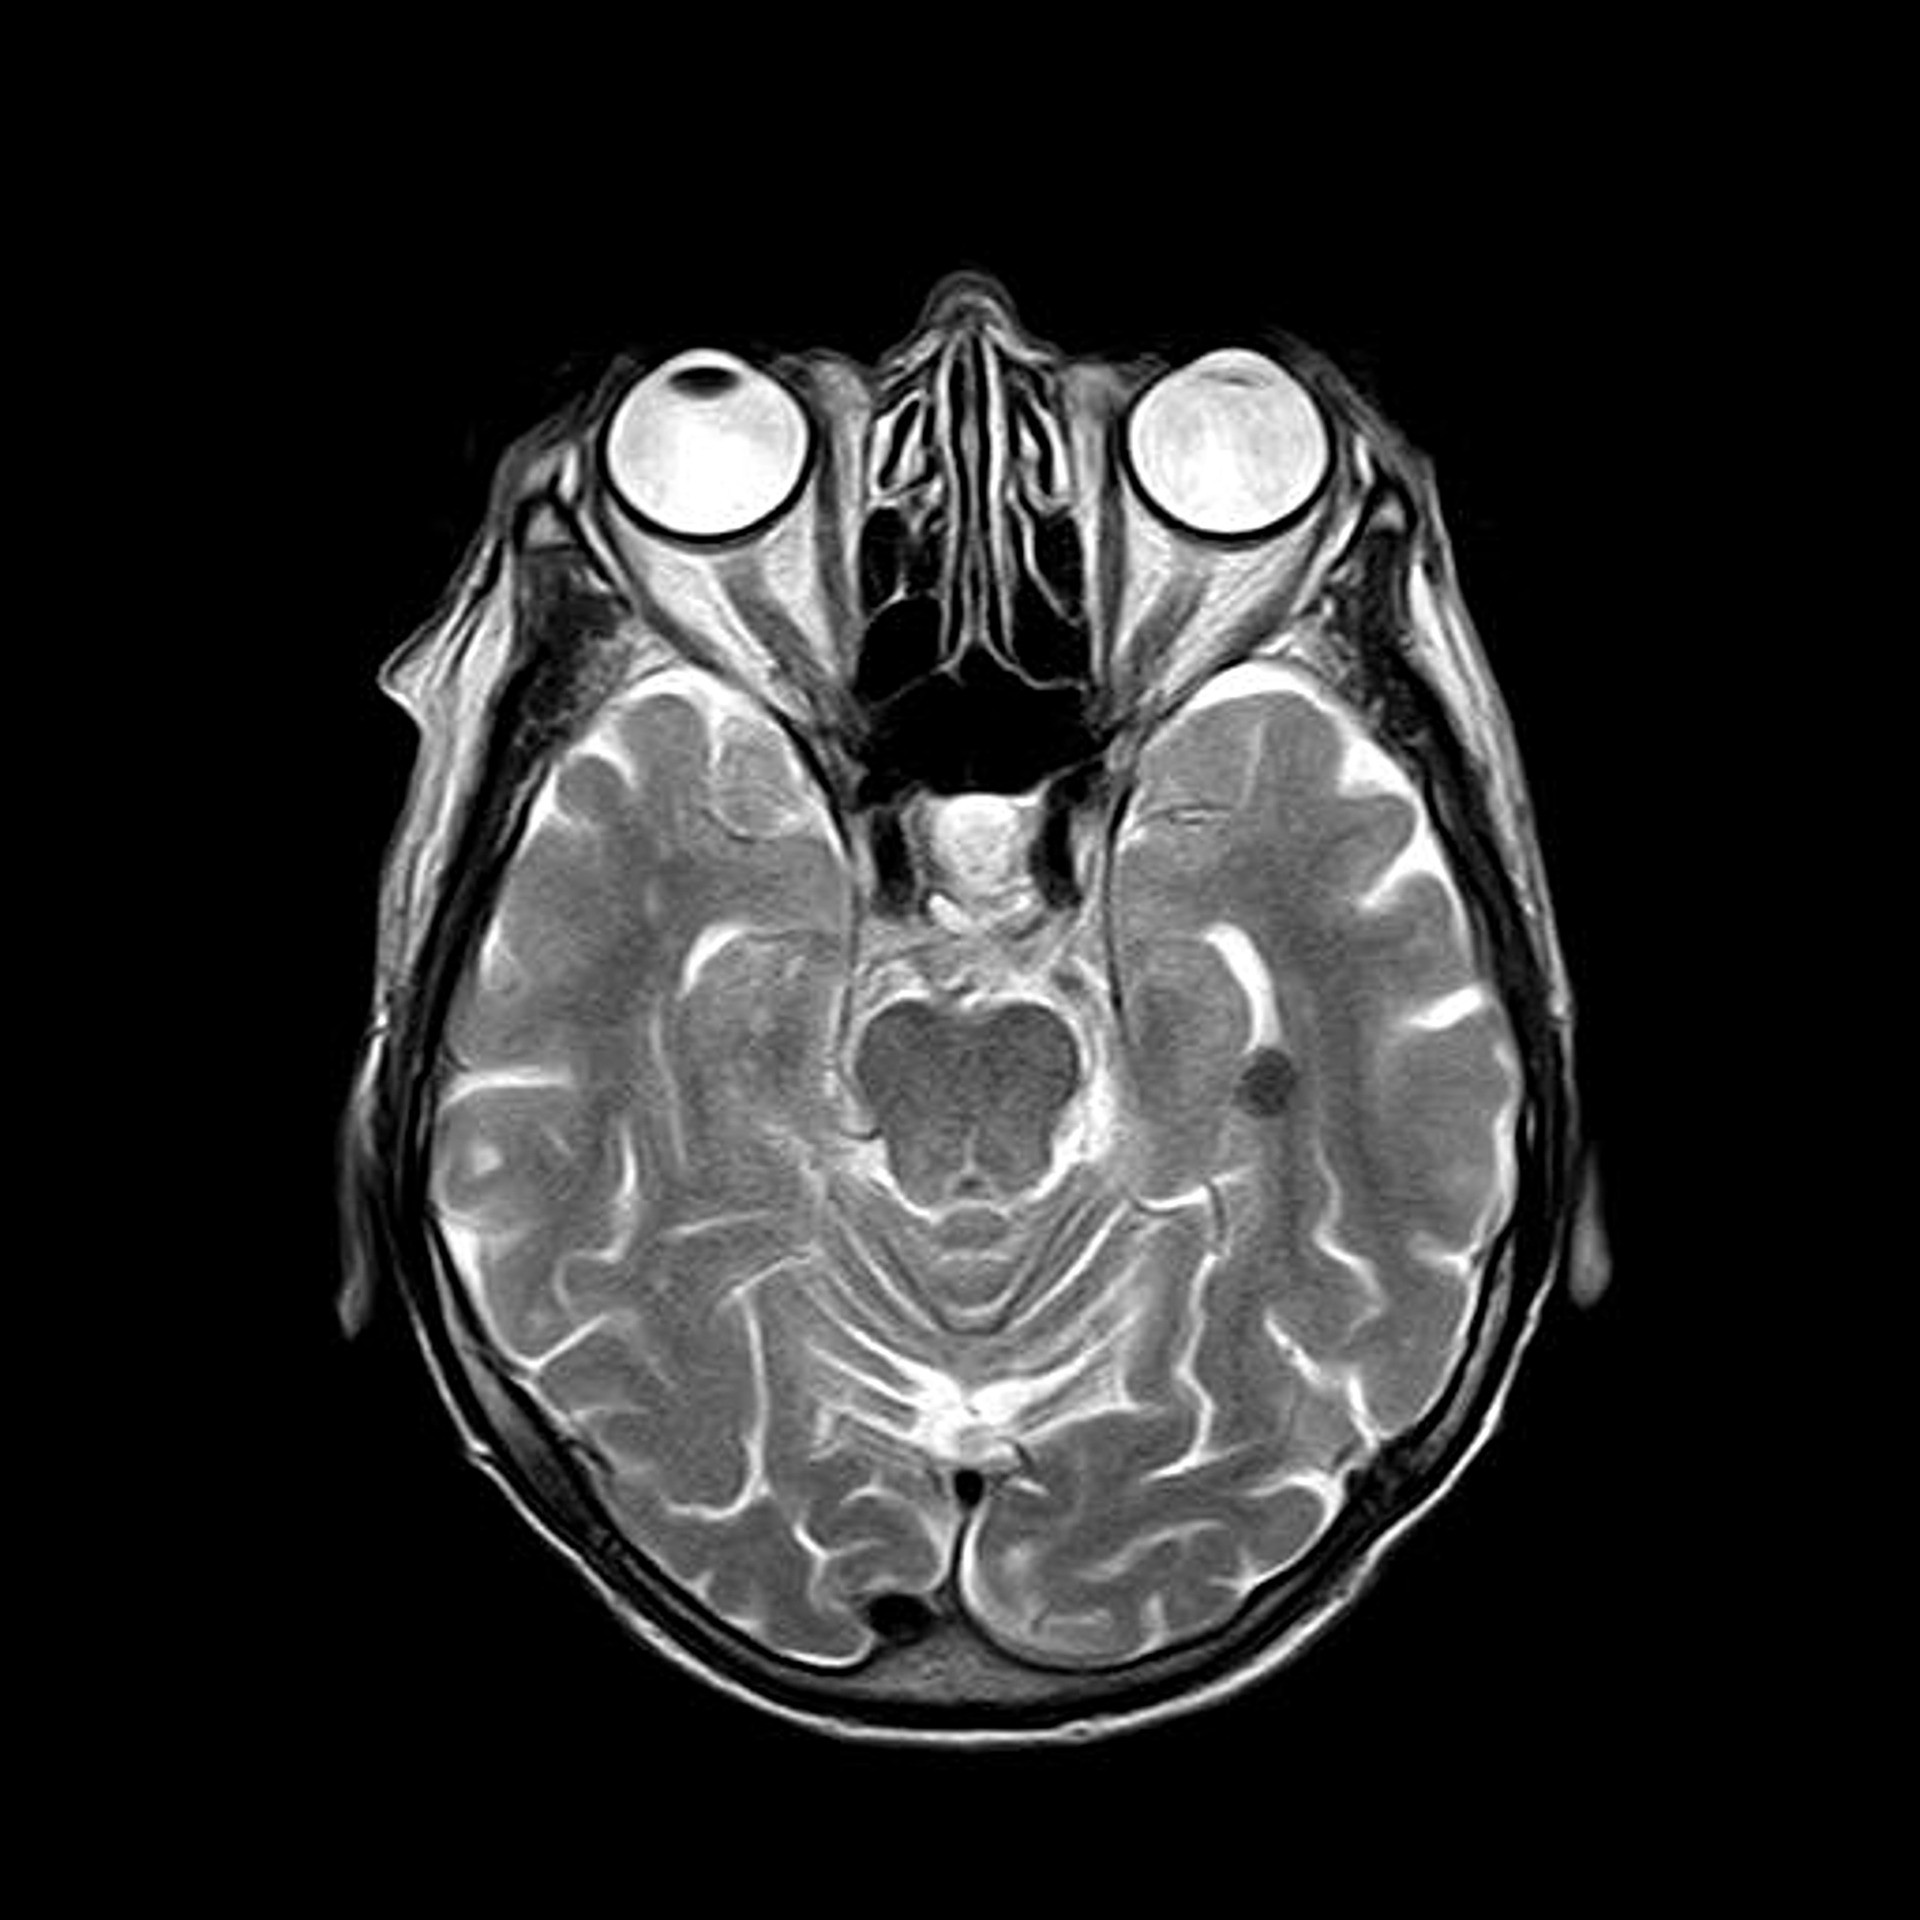

The idea is very simple, we have original DICOM image as seen left, and we are going to add some random noise to make the image look like right.